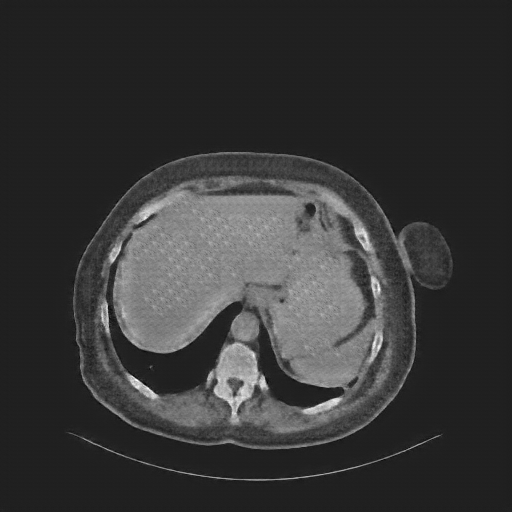

Reconstructed NATIVE CT scan (cycle consistency)

Full window (WL 1023.5, WW 4095 β†’ Low βˆ’1024, High +3071)

Actual HU range: [-620.4, 433.1]

Lung window (WL -600, WW 1500 β†’ Low βˆ’1350, High +150)

Actual HU range: [-620.4, 150.0]

Mediastinum window (WL 40, WW 400 β†’ Low βˆ’160, High +240)

Actual HU range: [-160.0, 240.0]